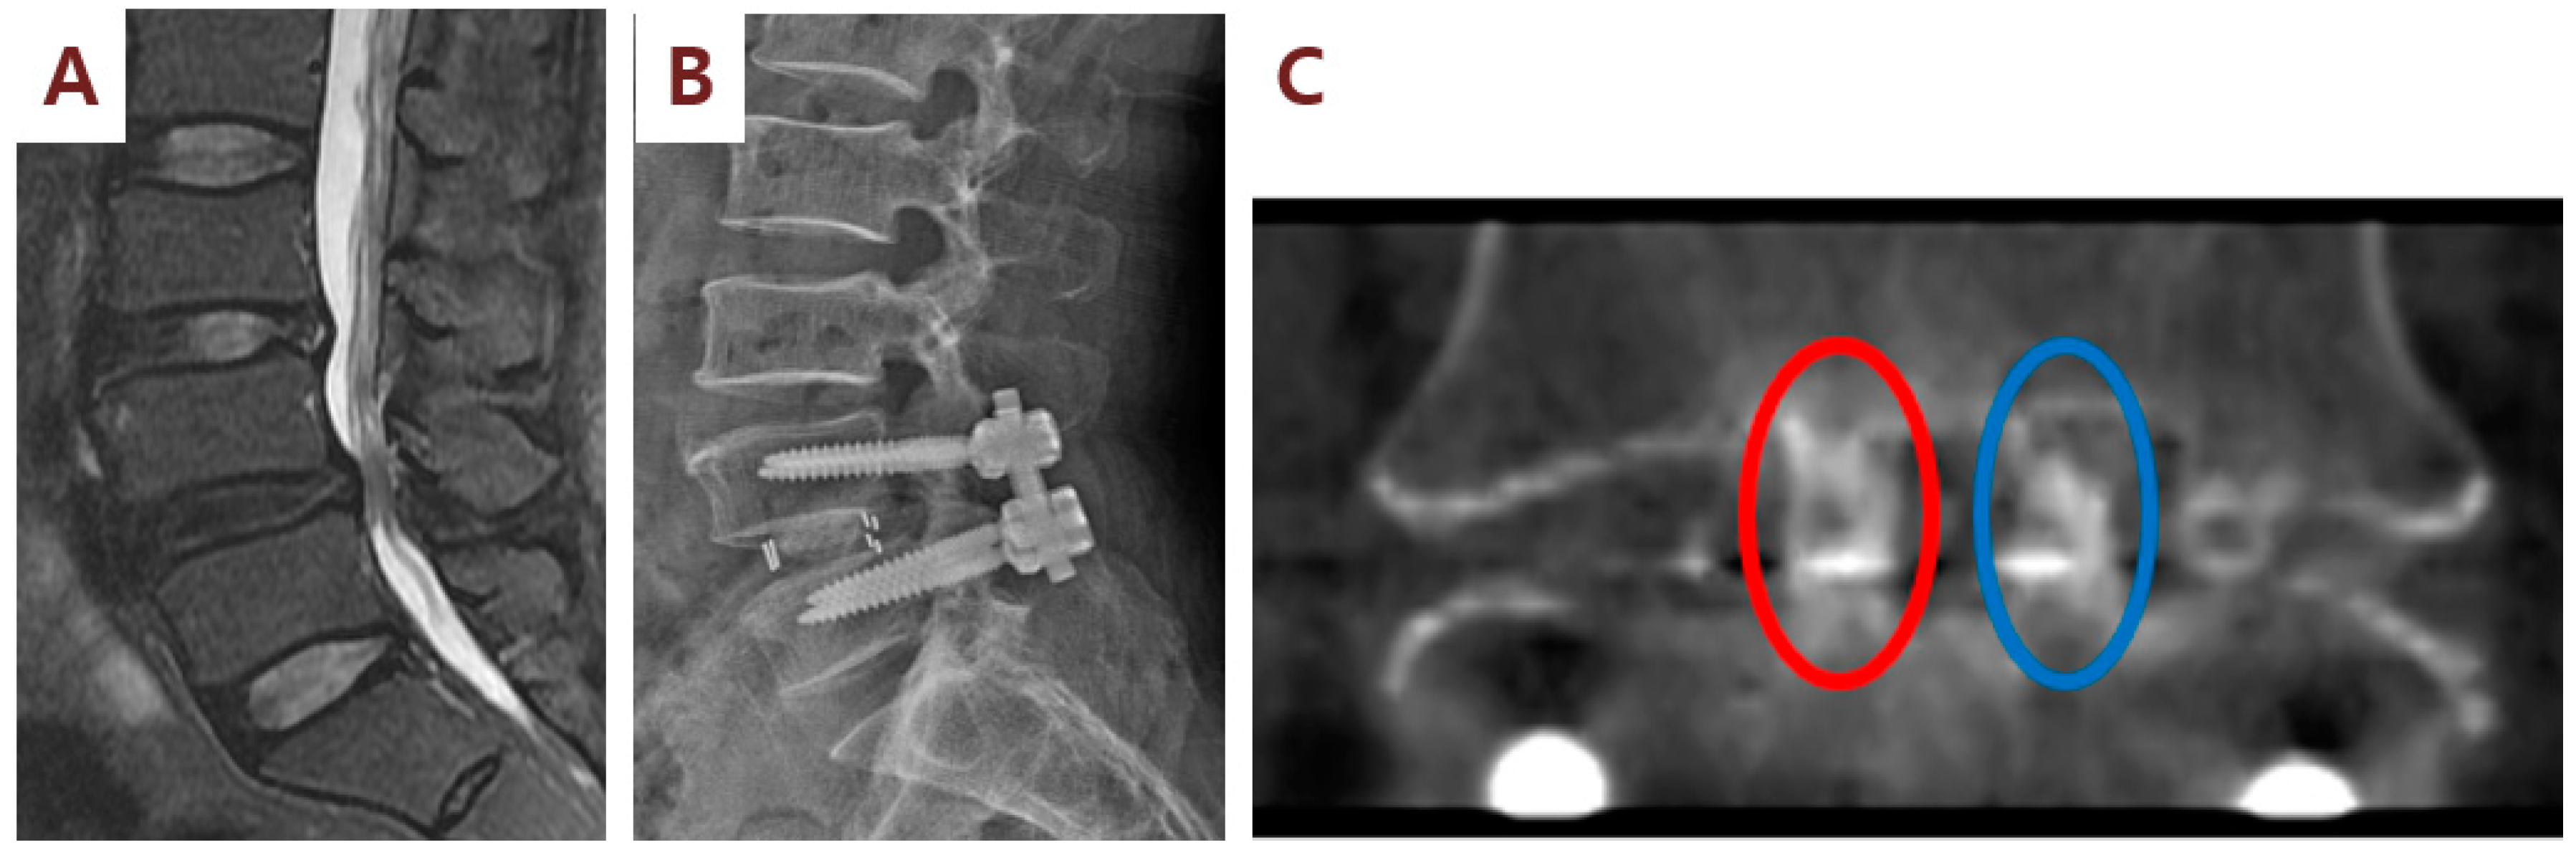

Figure 5.

Illustration case (Patient No. 3): A 63-year-old male received posterior lumbar interbody fusion and pedicle screw fixation. (A) Preoperative lumbar sagittal MRI demonstrating L4/L5 severe spinal stenosis. (B) Postoperative lumbar spine standing lateral view. (C) CT coronal view at 6 months after surgery showed the fusion status of cages (red eclipse) filled with SVF and β-TCP mixture on the right side of the patient. By contrast, CT coronal image showed no fusion status (blue eclipse) of cages filled with β-TCP alone on the left side.